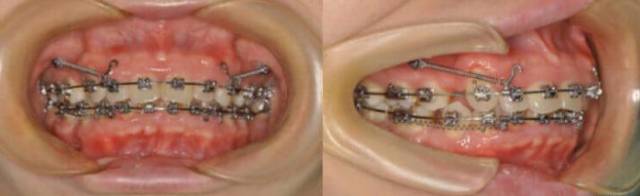

下面是口内矫正效果照片:

牙齿矫正后,女孩容貌有了很大改善,露龈笑情况消失了,人看着都年轻了好几岁,笑容也变得自然优美,侧貌也不再突出,显得人更加有气质,最重要的是,牙齿咬合健康稳定,口腔问题也有很大改善。